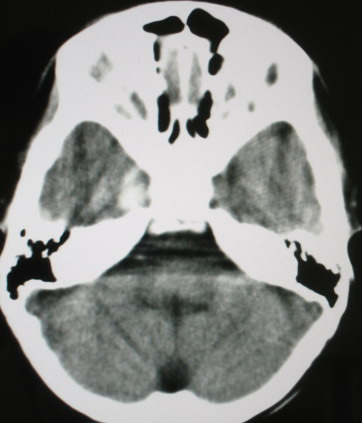

m/8y/,右侧眼睑下垂数日,发育良好,无外伤史,无头痛、恶心、呕吐,学习成绩良好。

ct意见:1、颅内血管畸形。2、右侧海绵窦血管瘤(颈内动脉海绵窦段动脉瘤)。3、脑萎缩。4、建议mr或dsa.

平扫片(骨窗未见异常)